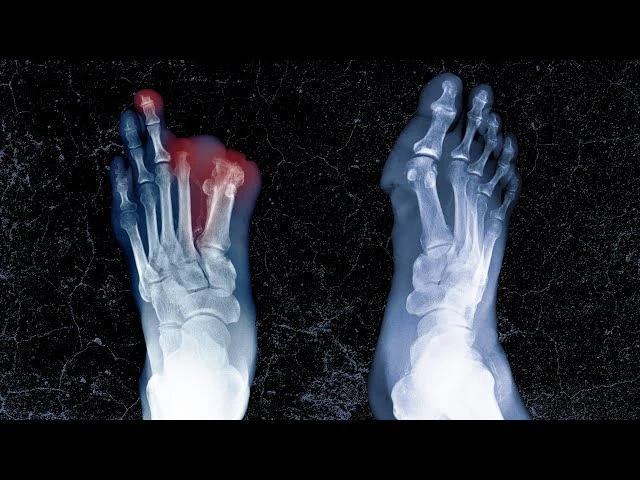

Nam sinh viên được chẩn đoán mắc vi khuẩn neisseria meningitidis, loại vi khuẩn khiến bệnh nhân bị tê liệt phần cổ, buồn nôn, suy hô hấp, sốc và suy đa cơ quan. Ảnh: INDEPENDENT